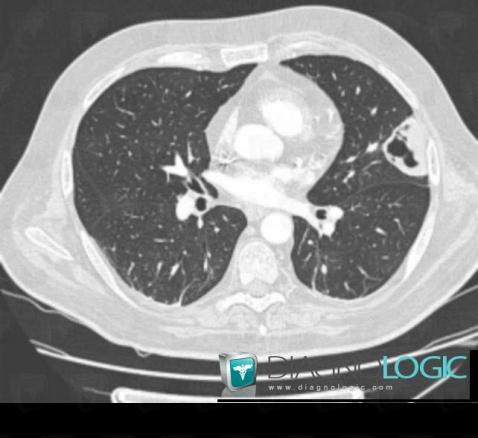

Pneumocystosis, Pulmonary parenchyma, CT

Here is the specific information in the key image above:

- Diagnosis Pneumocystosis, Location(s) Pulmonary parenchyma, with gamuts Cavitary pulmonary nodule, Multiple pulmonary nodule, Intracavitary pulmonary nodule / mass